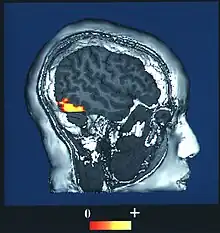

Prosopagnosia (from Greek prósōpon, meaning "face", and agnōsía, meaning "non-knowledge"), also known as face blindness,[2] is a cognitive disorder of face perception in which the ability to recognize familiar faces, including one's own face (self-recognition), is impaired, while other aspects of visual processing (e.g., object discrimination) and intellectual functioning (e.g., decision-making) remain intact. The term originally referred to a condition following acute brain damage (acquired prosopagnosia), but a congenital or developmental form of the disorder also exists, with a prevalence of 2.5%.[3] The brain area usually associated with prosopagnosia is the fusiform gyrus,[4] which activates specifically in response to faces. The functionality of the fusiform gyrus allows most people to recognize faces in more detail than they do similarly complex inanimate objects. For those with prosopagnosia, the method for recognizing faces depends on the less sensitive object-recognition system. The right hemisphere fusiform gyrus is more often involved in familiar face recognition than the left. It remains unclear whether the fusiform gyrus is specific for the recognition of human faces or if it is also involved in highly trained visual stimuli.

| The fusiform face area, the part of the brain associated with facial recognition | |